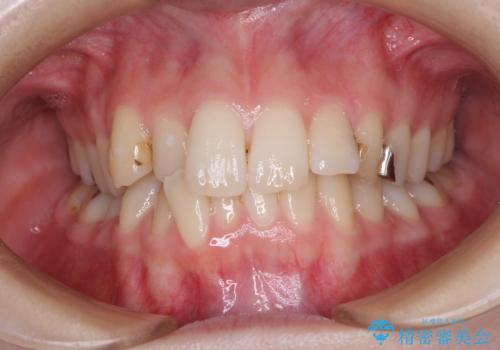

前歯のクロスバイトと治療が必要なむし歯 矯正とセラミックの総合歯科治療